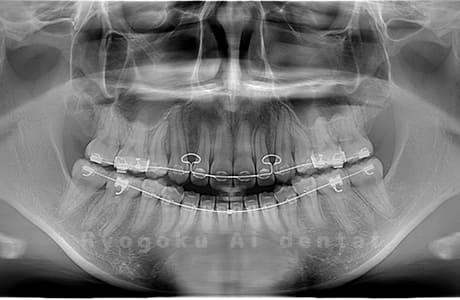

Case04

- 原因

- 上顎の親知らず、下顎の水平埋伏の親知らず

- 治療内容

- 上顎の親知らず、下顎の水平埋伏の親知らずを抜歯したケースです。

<リスク・副作用>

手術後は痛み、腫れ、痺れなどの副作用が生じる場合があります。